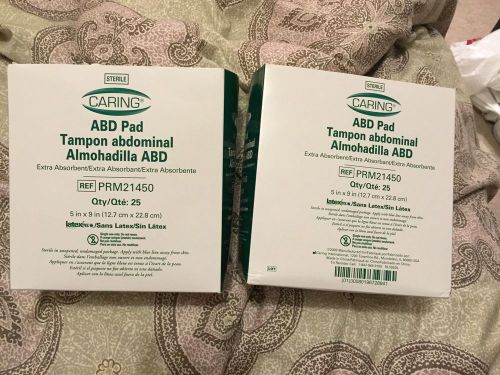

Caring ABD Pad ref nun PRM 21450 50 Count